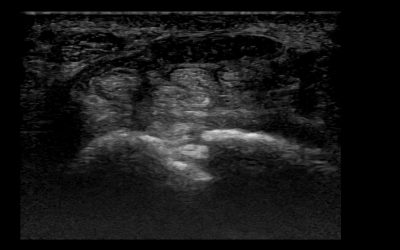

Ultrasound of nerves does have some special requirements as we are assessing small to very small structures. While “bigger” nerves like the median or ulnar nerve present with cross-sectional areas (CSA) from 8 to 15 mm2 and do therefore not impose a major problem in...